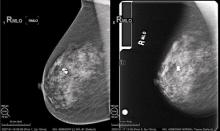

Lying chest down, head turned to the side, breast suspended through a cutout in the table, women can routinely get a mammogram with computed tomography (CT). An alternative to tomosynthesis and potentially even magnetic resonance imaging (MRI), the 360-degree scan can be completed in 10 seconds.